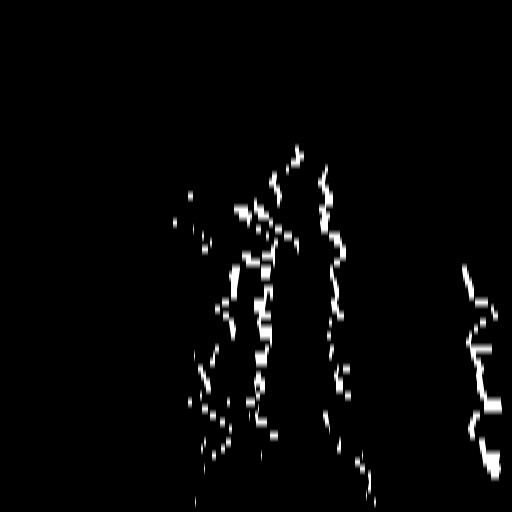

Parallel vessel motion loss .

We conduct an experiment to assess the effect of the parallel vessel motion loss by removing it from the training pipeline. As shown in Table 2, the segmentation performance decreases the Dice score by 0.0368. Without this loss to enforce parallelism between blood and vessels, the segmentation results are negatively affected. In addition, the comparison between without and with is shown in Figure 9 (c). The zoom-in patch shows that the image with has clearer segmented vascular regions.